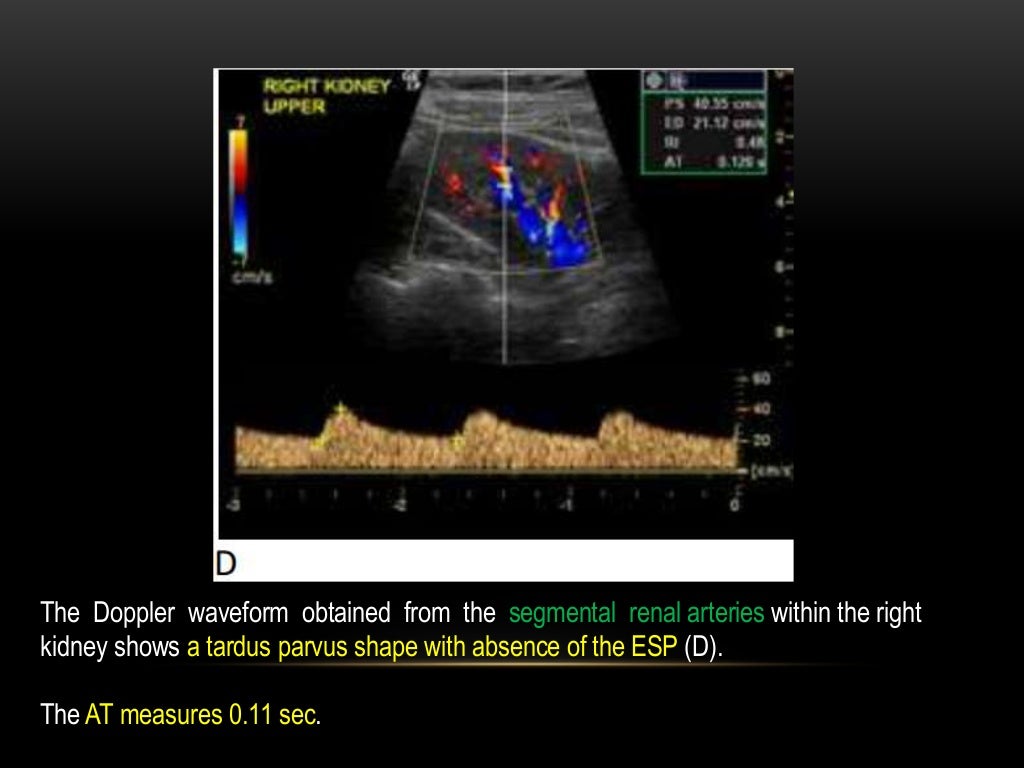

WebLa ecografía Doppler es una prueba no invasiva que calcula el flujo de la sangre en los vasos sanguíneos haciendo rebotar ondas sonoras de alta frecuencia. WebSi te van a realizar una ecografía-doppler estas son las cuestiones que debes tener en cuenta: Duración : la ecografía-doppler dura unos 15 minutos. Ingreso : se suele realizar. WebDE LA ARTERIA RENAL MEDIANTE DOPPLER La estenosis de la arteria renal mediante la técnica Doppler se detecta de dos formas: 1) por la alteración de la forma de onda en.